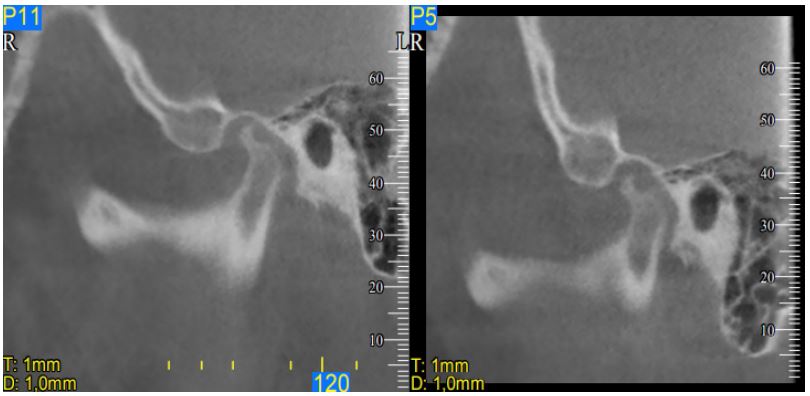

On presentation, the patient had a panoramic radiograph, where the TMJ depicted rather atypical (Figure 4). The diagnostic process could not rely on this x-ray, due to the overlaps with other anatomical elements in the region; this additional imaging techniques deemed necessary [14]. The Cone beam computed tomography (CBCT) which was selected in this instance, revealed on the right side that the condyle was centrally positioned, while erosive lesions were seen in the upper anterior region of the condyle at the medial pole. Microerosions at the outer pole could not be ruled out. Early to moderate degenerative alterations were consistent with this image (Figure 5).

On the left side, the condyle was posteriorly displaced, although the joint space remained within the expected range. An extensive erosive lesion, approximately about 5 mm in diameter was evident in the posterior- superior portion of the condyle. This lesion occupied the whole middle third of the condyle head and was surrounded by a sclerotic margin. This image was indicative of a higher degree of degenerative alterations (Figure 6).

Figure 5: The cone beam computed tomography (CBCT) image of the right TMJ in close mouth position. The condyle was centrally positioned, while erosive lesions were seen in the upper anterior region of the condyle at the medial pole. Microerosions at the outer pole could not be ruled out. Early to moderate degenerative alterations were consistent with this image.

Figure 6: The cone beam computed tomography (CBCT) image of the left TMJ in close mouth position. The condyle was posterior displaced, and an extensive erosive lesion (arrow), approximately about 5 mm in diameter was evident in the posterior- superior portion of the condyle. This lesion occupied the whole middle third of the condyle head and was surrounded by a sclerotic margin. This image was indicative of extensive degenerative alterations.

Figure 7: The cone beam computed tomography (CBCT) image of the right TMJ in close (left) and open (right) mouth position (close view). During opening, the right condyle exhibited displacement sliding on the posterior part of the articular eminence, although not to a fully extent, suggesting diminished range of motion.

Figure 8: The cone beam computed tomography (CBCT) image of the left TMJ in close (left) and open (right) mouth position (close view). During opening, the condyle performed only rotational movement around its hinge axis, without any displacement sliding on the posterior part of the articular eminence. This finding is compatible with a clearly limited opening movement. Compare to the right side. Notice also the extent of the erosion.